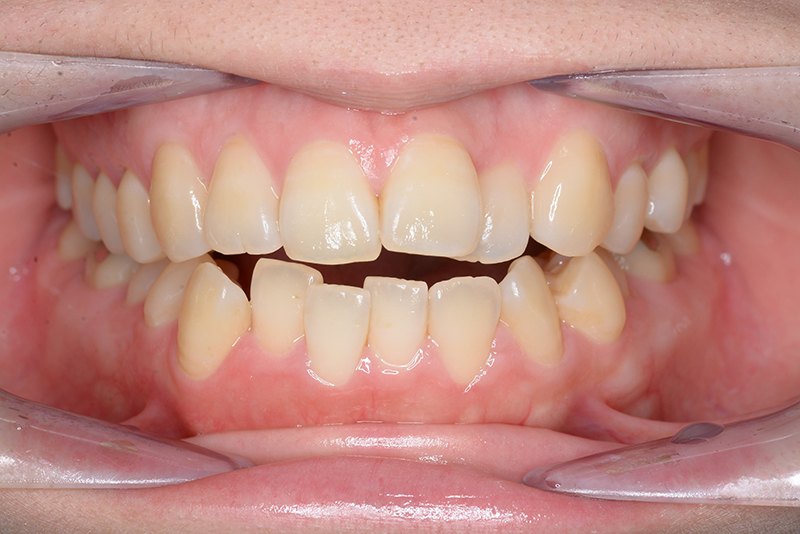

| 主訴 | 前歯で物が噛めない | 診断名 | アングルⅠ級開咬症例 | ||||

| 初診時年齢 | 37歳8ヵ月 | 性別 | 女 | 動的治療期間 | 23ヵ月 | ||

| 口腔内所見 | 臼歯関係はⅠ級、over jet 4.5mm、over bite -3.0mm。上下顎切歯部に軽度の叢生が認められ唇側傾斜をしつつ開咬を呈していた。 |

| 批評・予后 | 治療後において下顎角の開大も認められず歯軸の整直、咬合の緊密化が得られた。また上下顎前歯の後退と共に口元の突出感と口唇閉鎖不全の改善が認められた。 |